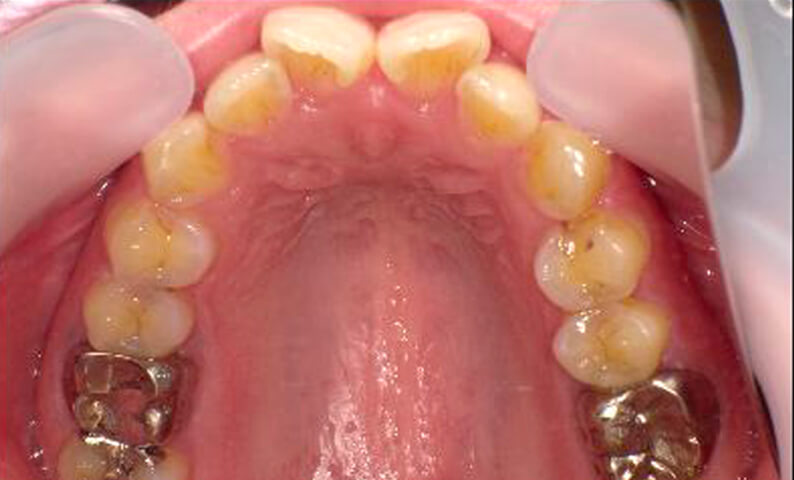

症例_003 上下顎の部分矯正

治療期間:12ヶ月金額:54万円+税男性八重歯前歯のガタガタ

| Before | After |